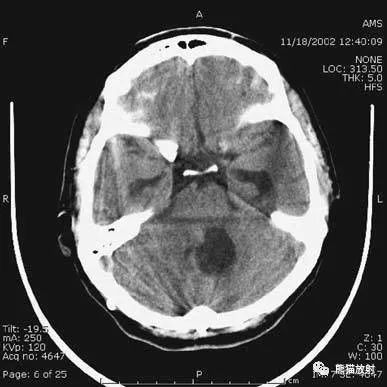

2、鞍上池层面颅前窝:颞叶。

鞍上池:在垂体窝上方,位于两侧颅中窝之间,前界为颞叶直回,侧方位颞叶海马,呈五角星形或六角星形。其前角连于纵裂池,两外侧角连于外侧裂池,两后外侧角延续于环池,第六个角位于后缘中间,是角间池。鞍上池边缘为大脑动脉环,池内前部常可见“V”字形视交叉。

颅后窝:四脑室或四叠体池。